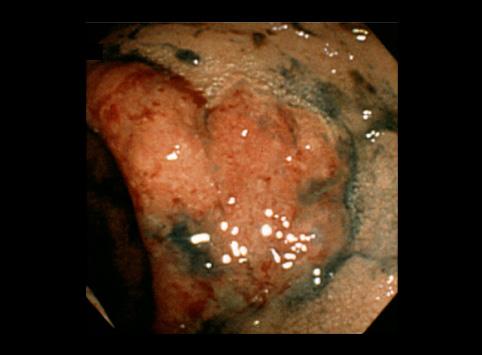

疾病(病理主体)的分类炎症性・溃疡性疾患/其他

部位(按器官分)大肠/直肠

检查方法内窥镜

肿瘤最大直径10~14